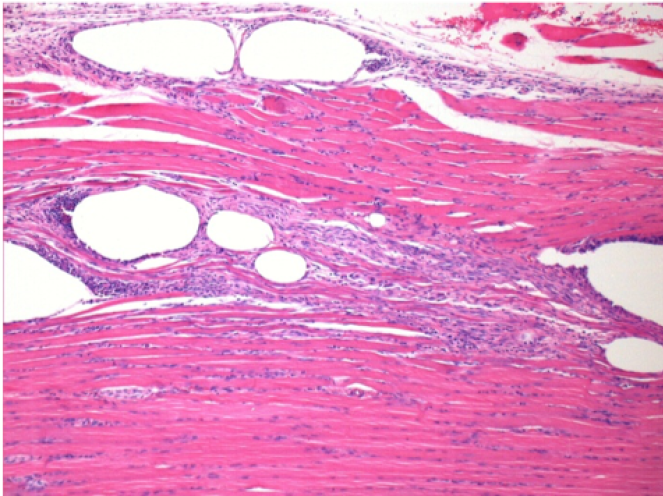

10 days after Endopeel Injection

10 days after Endopeel Injection 0.1ml in the right pretibial muscle.

Here you may see the formation of the vacuoles which are surrounded by lymphocytes. Vacuoles are different from tissue necrosis . The presence of lymphocytes is related to the permeability of the cell membranes.

L : Control-100xD10

R:100xD10

R :200xD10

R :400xD10